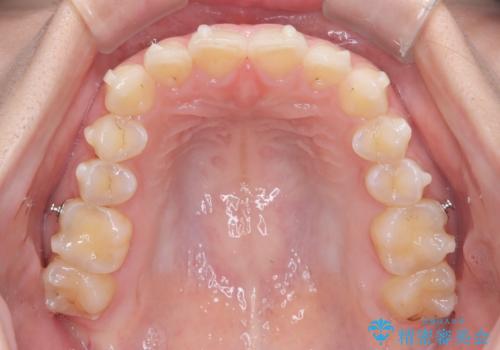

- 前歯のガタガタが気になるとのことでご相談いただきました。診察すると、歯列のスペースが不足し、前歯が重なっている状態でした。抜歯をせずに整えるため、歯と歯の間をわずかに削るIPR(歯列幅径削除)と、奥歯を後方へ動かす遠心移動を組み合わせてスペースを確保しながら並べる治療計画を立てました。

インビザラインを用いて歯を少しずつ移動させながら、IPRで微調整を行い、スペースを確保しました。また、奥歯を遠心移動させることで、前歯を自然な位置に並べることができました。治療後は、「ガタガタがなくなり、スムーズな歯並びになった」と患者様にもご満足いただきました。